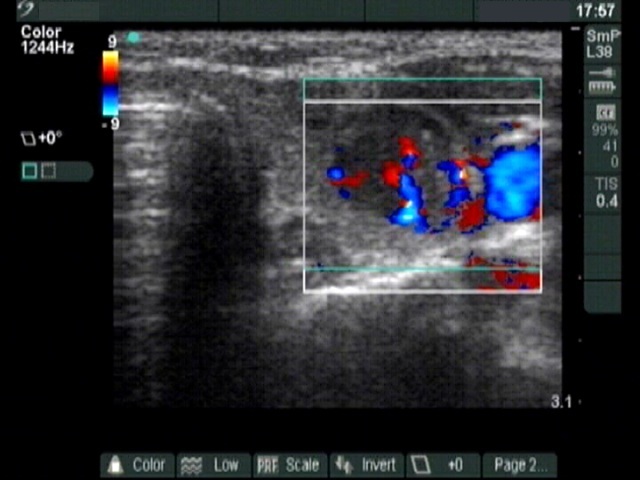

Thyroid cancers - case 185 (ultrasonographic picture 6)

Left lobe, transverse scan, color Doppler mode. The lesion is hypervascularized.